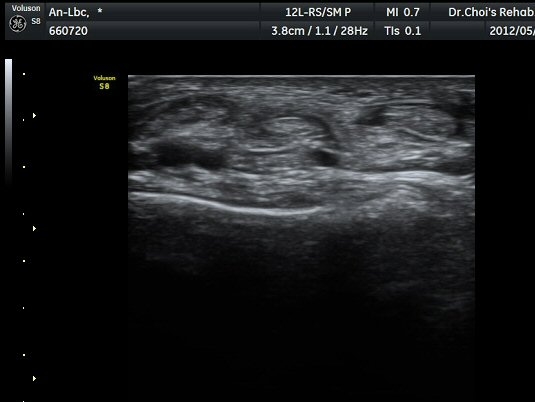

¹ß¸ñ ¾Õ Ⱦ´Ü¸é°Ë»ç¿¡¼­ Àü°æ°Ç(TA), ¾öÁö½ÅÀü°Ç(EPL), ¹ß°¡¶ô½ÅÀü°Ç(EDL)ÀÇ ºÎÁ¾ ¹×

°Ç ÁÖÀ§ ¼ö¾× Àú·ù°¡ °üÂûµÈ´Ù(»çÁø 1, 2). °ÇÀÇ ºñÈÄ¿Í ¼ö¾×Àú·ù´Â °ÇÃø(»çÁø 4)°ú ºñ±³Çϸé

¶Ñ·ÈÇÏ´Ù. Àü°æ°Ç Á¾´Ü¸é°Ë»ç¿¡¼­ °ÇÀÇ ºÎÁ¾°ú °Ç ÁÖÀ§ ¼ö¾× Àú·ù°¡ °üÂûµÈ´Ù(»çÁø 3). °ÇÀÇ

ºÎÁ¾°ú ¼ö¾×Àú·ù´Â °ÇÃø°ú ºñ±³ÇÏ¸é ¶Ñ·ÈÇÏ´Ù(»çÁø 5).¤·